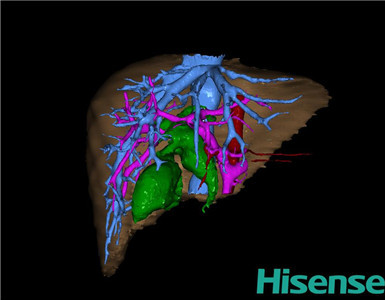

CT结果输入海信CAS系统后行3D重建及手术规划后,于2014-9-16全麻下行“胆总管囊肿切除+胆囊切除+胆总管-空肠吻合术”手术治疗:

术前三维重建及手术方案设计:

将0.625mm双源薄层CT资料的静脉期和动脉期Dicom格式文件导入海信CAS系统。

通过调节窗宽窗位调整CT序号,对肝实质,胆囊,下腔静脉,肝动脉、门静脉及肝静脉等进行三维重建;系统自动计算肝脏体积。

术前三维重建:

重建图片